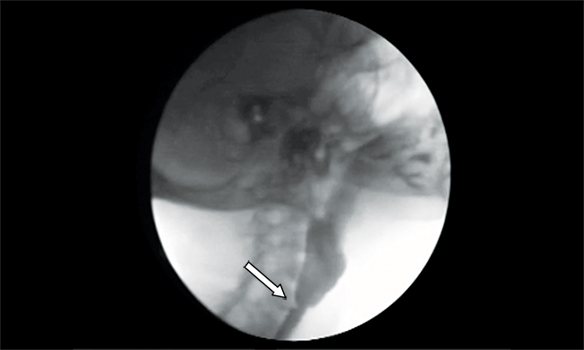

Se efectuó un tránsito esófagogastroduodenal (TEGD) que reveló a nivel esofágico superior la presencia de una ligera membrana que no impedía el pasaje del material de contraste (Figura 3). Se programó la realización de una videoendoscopía digestiva alta (VEDA), objetivándose la presencia de una membrana grisácea en el tercio superior esofágico, la cual ocupaba menos del 25 % de la circunferencia (Figura 4).